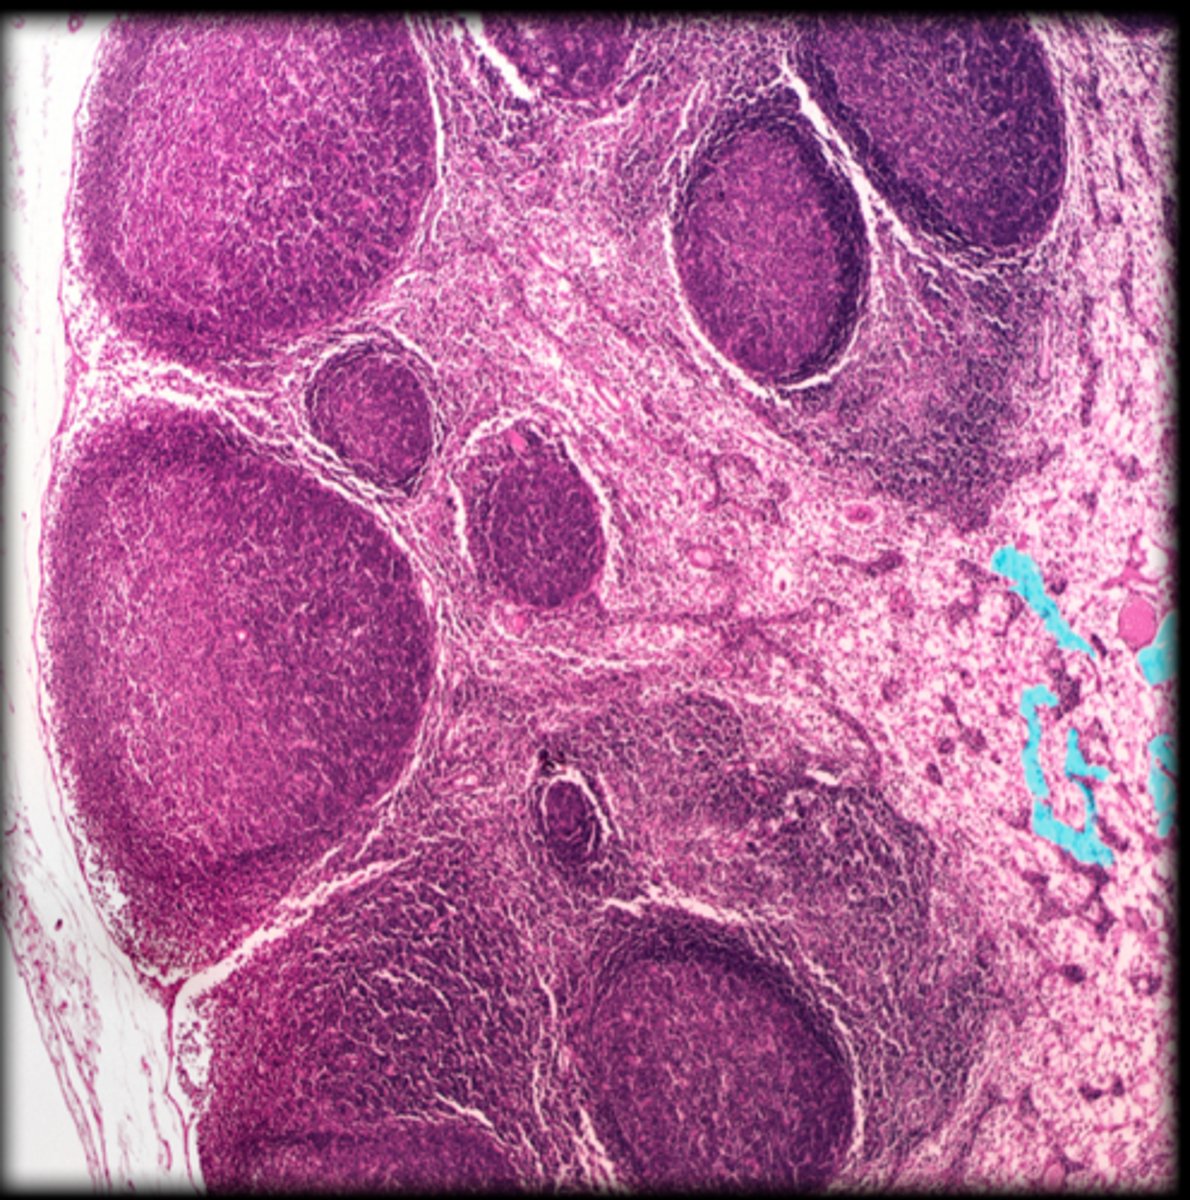

capsule

Lymph node

cortex

medulla

medullary cord

-There are some T-lymphocytes and macrophages are collected here.

medullary sinus

-This area is filled with lymph.